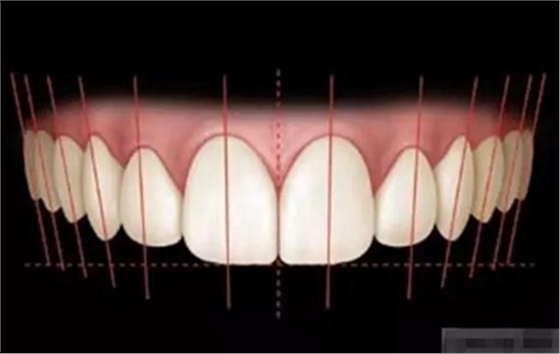

審美序列清單:

1、切牙的位置長度

前牙的黃金分割比例

正面觀

側(cè)切牙約為中切牙的60%

尖牙約為側(cè)切牙的60%

5.外展隙:切端.頸部.唇側(cè)和舌側(cè)